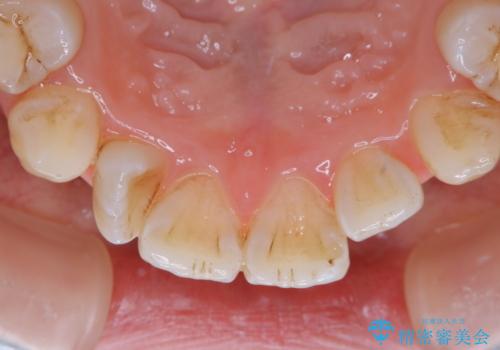

- インビザラインでの矯正治療中の方です。全体的に黄ばみ・黒ずみが気になるとのことでした。

PMTC(保険外治療)は、毎日の歯磨きで落としきれない汚れや、コーヒ、紅茶・タバコのヤニなどの着色も除去します。目には見えない歯と歯の間・歯肉の境目・インビザライン中はアタッチメント周囲などに残っているプラーク(歯垢)もしっかり取り除きます。PMTCでは専門的な機械や材料を使用して、徹底的に汚れを除去するため、虫歯・歯周病・口臭予防などにつながります。